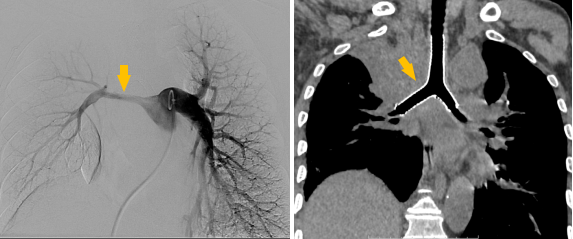

介入手术室里,一场无声的战役打响。麻醉科主任闫华凭借高超技术,成功为患者通气建立安全通路,为手术的实施奠定基石。介入科主任贺光辉带领团队细致操作,将一枚Y形气管支架在X线引导下输送至预定位置后精准释放,原本被肿瘤挤压得只剩一丝缝隙的气道被稳稳地撑开。紧接着一枚肺动脉覆膜支架置入到受压变窄的右肺动脉主干内并准确释放,再次造影,使得右肺动脉血流迅速得到改善。

手术过程

同期置入支架后狭窄明显改善